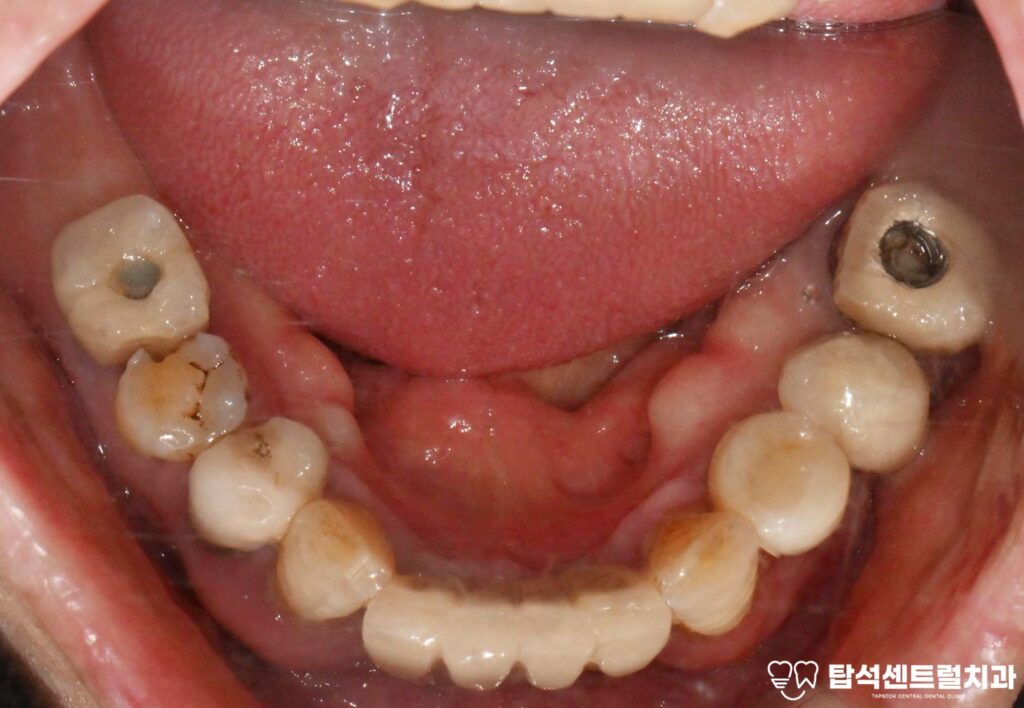

골소실이 심하게 진행된 고정체는

보존이 어려워 제거해야 될 수 있습니다.

흔들리는 상태에서 무리하게 사용하면

주변의 건강한 뼈까지 손상될 수 있기 때문입니다.

제거한 픽스처의 모습입니다.

염증이 퍼지면서 인접한 자연치아나

다른 고정체에도 영향을 줄 수 있어,

적절한 시기에 결단을 내리는 것이 중요합니다.